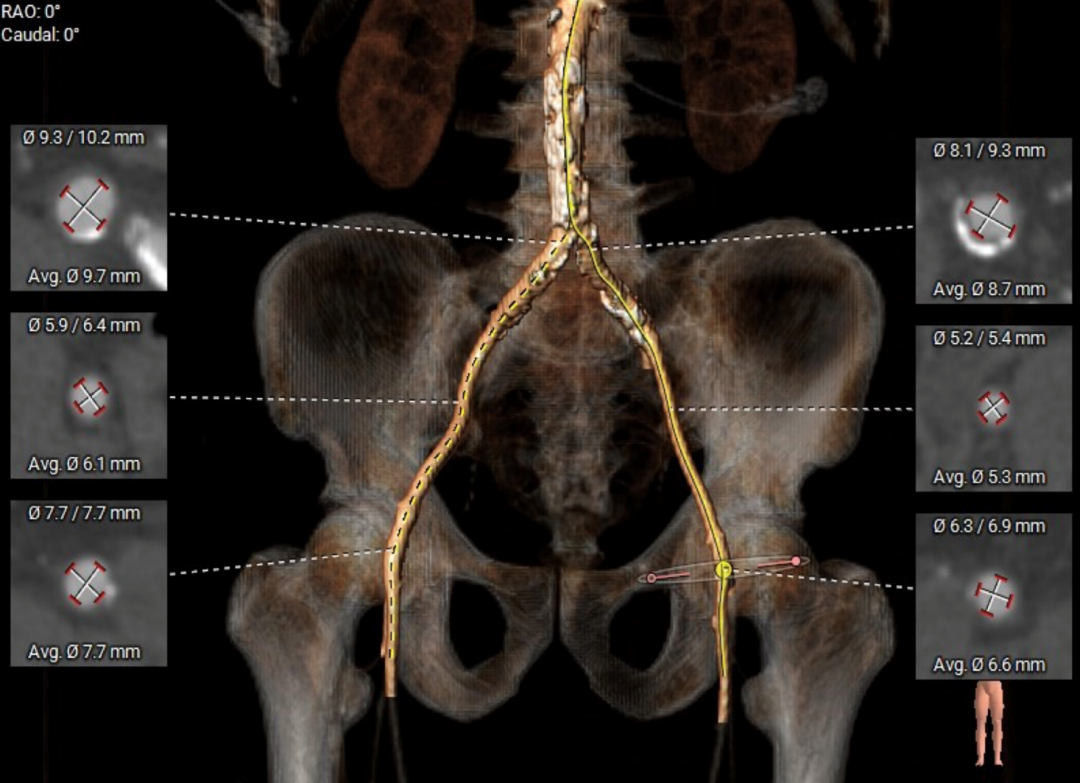

主动脉根部测量

ANNULUS

SOV DIAMETER

LVOT

STJ

ASCENDING AORTA

LEFT VENTRICLE

CT数据显示该患者为Type0主动脉瓣。

主动脉瓣瓣环周长97.1mm,平均周长径 30.9mm,SOV:34.8mm*47.5.3mm*42.4mm,瓣叶增厚,瓣上钙化分布不均,瓣环水平夹角66°。

冠脉高度测量

LEFT CORONARY

左冠开口高度20.4mm

RIGHT CORONARY

右冠开口高18.8mm

钙化分布:HU850钙化积分881mm³

左心室影像

外周血管及主动脉弓解剖

双侧血管内径良好,所见腹主动脉血管壁钙化形成